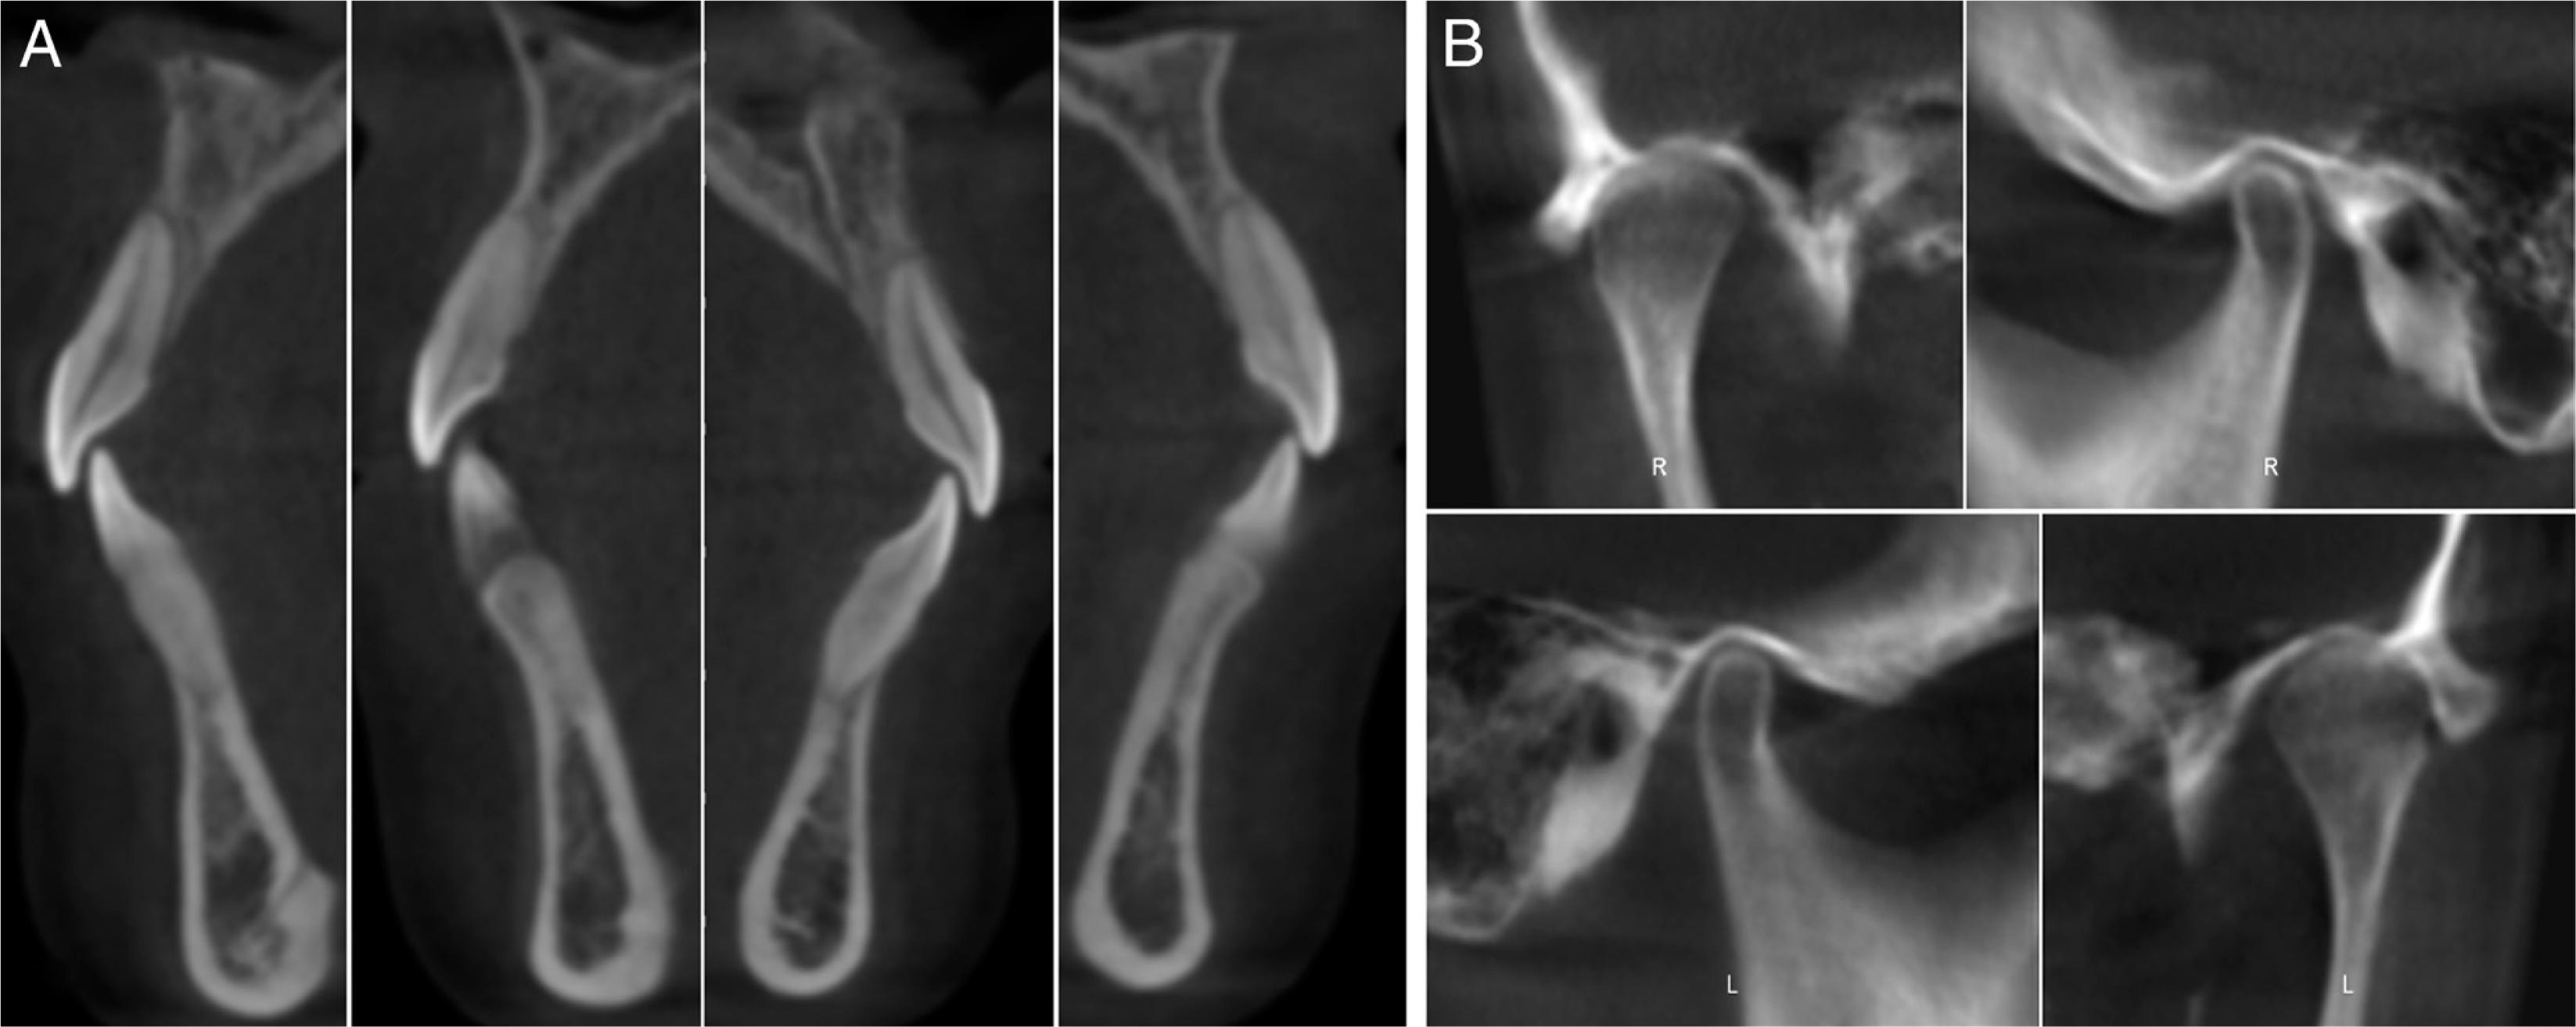

Figure 2.